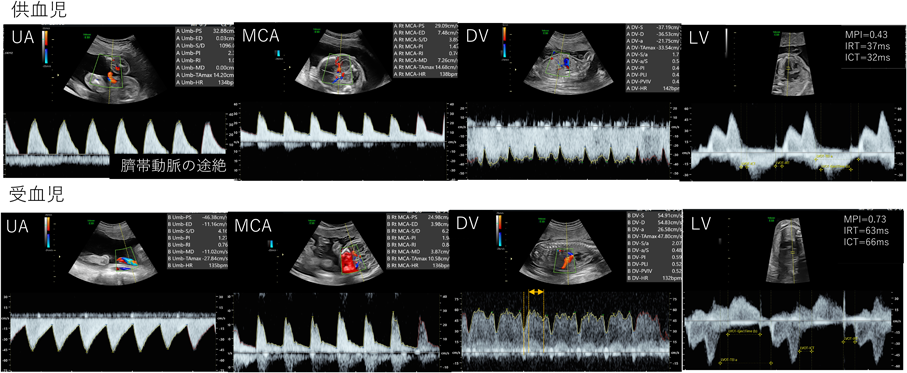

TTTSの受血児では供血児からの血液とレニン,アンギオテンシン,アルドステロンなどの血管作動性のホルモン(RAASホルモン)の移行を受けて,前負荷・後負荷が共に増大する.胎盤の吻合血管を遮断することで循環動態を改善させるfetoscopic laser photocoagulation(FLP)による胎児治療で,周産期予後は劇的に改善してきている.TTTSのステージ診断においては羊水量や臍帯動脈や静脈管といった動静脈ドプラ,胎児水腫の有無が評価項目となっているが,治療の前後においても胎児の循環動態は大きく変化するため,胎児の心機能評価は重要となる.特に拡張能の評価が循環動態の改善を鋭敏に捉えることが知られており,受血児でのMPIの上昇やIRTの延長,E/e′の上昇,また静脈管のS波のtime velocity integralの変化21, 22)などが報告されている(Fig. 7).また同時にFLP後のMPIの減少,MAPSEやTAPSEの増大も報告されている23)

Pediatric Cardiology and Cardiac Surgery 40(2): 103-112 (2024)

Fig. 7 双胎間輸血症候群(TTTS stage IIIa)の一例

DV=静脈管血流,MCA=中大脳動脈血流,LV=左室流入血流,UA=臍体動脈血流